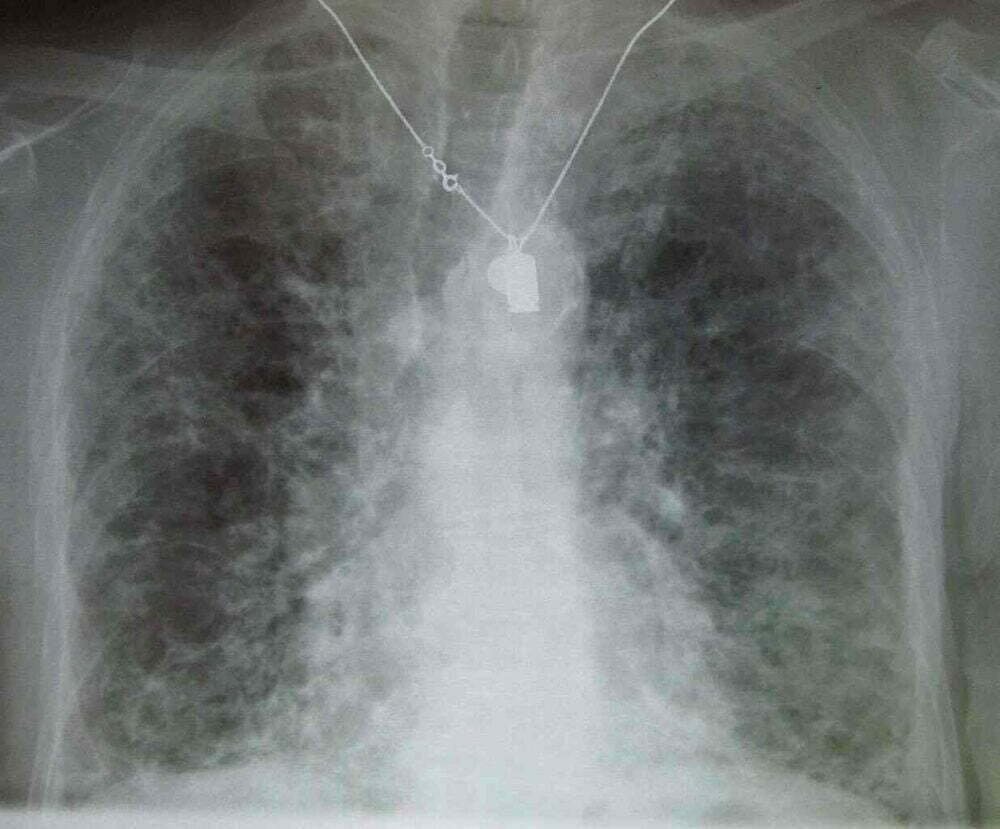

Diagnosis dapat dilakukan dengan menggunakan rontgen dada. Pemindai (scanner) paru-paru adalah pemeriksaan yang, pada sebagian besar kasus, memastikan adanya fibrosis. Jika ragu, biopsi paru dapat dilakukan (selama operasi atau selama fibroskopi bronkial).

Paru-paru dengan fibrosis paru stadium akhir saat otopsi. Penyakit paru interstitial stadium akhir menggambarkan sekelompok besar gangguan, yang sebagian besar menyebabkan jaringan parut progresif pada jaringan paru. Jaringan parut yang terkait dengan penyakit paru interstisial pada akhirnya memengaruhi kemampuan Anda untuk bernapas dan mendapatkan oksigen yang cukup ke dalam aliran darah. See page for author, Public domain, via Wikimedia Commons

Sumber foto utama: James Heilman, MD (CC BY-SA 3.0) via Wikimedia Commons

Deskripsi foto: rontgen dada menunjukkan fibrosis paru.